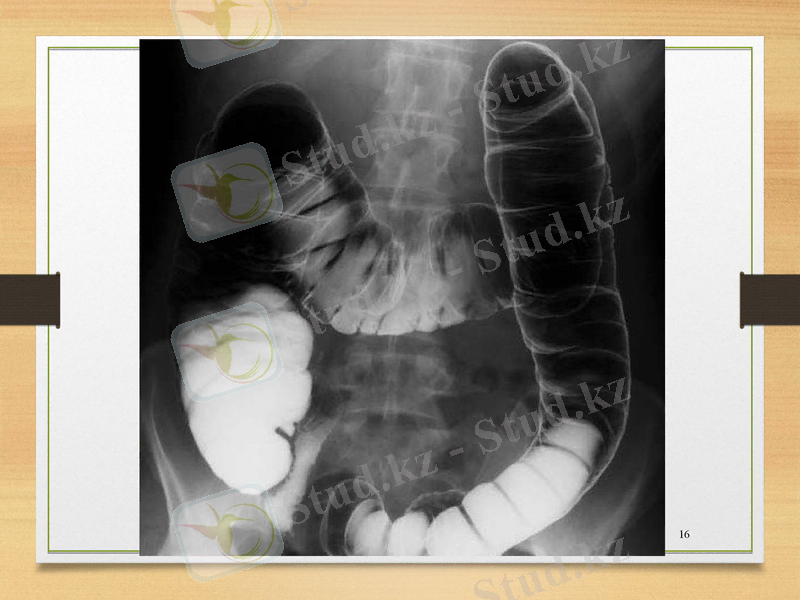

Бұндай белгілер пайда болған жағдайда клиникалық көріністерімен қатар, асқынуды анықтау және дәлелдеу шаралары ретінде рентгенологиялық зерттеу қолданылады. Онда ішек түйілу белгілері, Клойбер тостағаншалары т. б. анықталады. Егер сырғымалы жарықтың қысылуы болжанылса, оны дәлелдеу үшін ауру адамды зерттеу барысын ирригоскопия, цистоскопия тәсілдерімен толықтыру қажеттілігі тууы ықтимал.